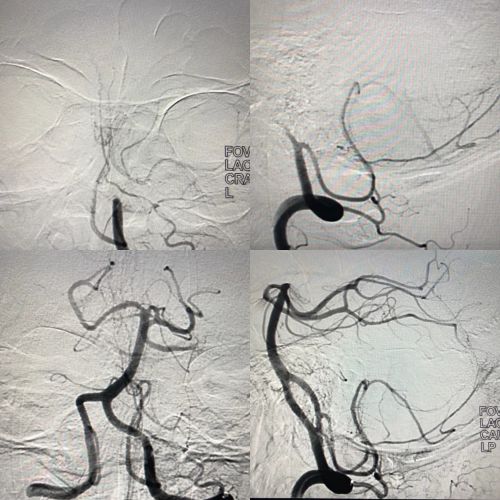

介入血管外科卒中团队为患者紧急实施脑血管腔内血栓取栓术

患者抵达前,岳麓山院区已为其开辟绿色急救通道,急诊脑血管中心医护人员提前在急诊等候。中午1215分,患者到达急诊,医护人员对其实施紧急评估,完成头部CT检查和抽血化验后,将其送至介入复合手术部。1225分,家属赶到但身上没带够钱,医护人员当即决定先救治后付费,家属在入院窗口只办理入院登记便获得住院号。1230分,捷克论坛 副院长、介入血管外科学科带头人向华教授,学科主任刘觉仕教授及康超文医生争分夺秒为患者实施局麻下脑血管腔内血栓取栓术。进入手术室28分钟后,患者再造影显示:受累血管血流恢复。12时58分,手术结束。

捷克论坛 岳麓山院区(湖南省急救中心)急诊脑血管中心,以航空救援、微创急救、尽速康复为特色。拥有最先进的西门子DSA+滑轨CTGECDSA机的介入复合手术部,可同时进行介入微创+开放手术治疗,高效的微创急救模式极大地缩短了急诊脑血管病从入院到检查、治疗、康复的时间。中心通过建立科学的急性脑血管病区域协同医疗急救体系,最大限度提高急性脑血管病救治成功率,降低病死率和致残率,打造湖南急诊脑血管病治疗技术高地。(急诊脑血管中心:阳秀春 康超文)